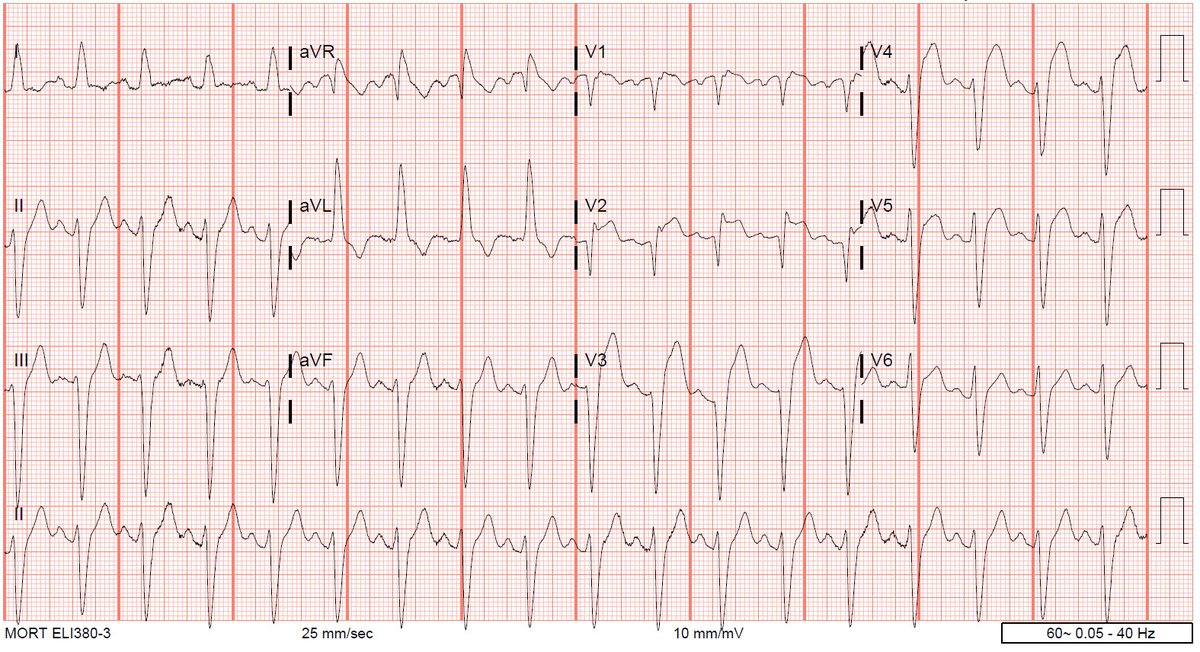

What’s the rhythm? First portion just looks like PACs in a pattern of bigeminy hitting a partially refractory AV node with resulting long PR. But why do the PAC PR intervals suddenly shorten at the end?@DidlakeDW @ecgrhythms @The_Nanashi_O #ECG #CardioTwitter